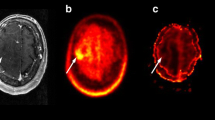

Progressive disease example of a patient with tumor progression, 7 months after initial diagnosis of anaplastic astrocytoma, resection and chemoradiotherapy the patient clinically deteriorated. Axial T1-weighted contrast-enhanced MRI (a) demonstrates right hemispheric progressive tumor tissue, corresponding PWI maps CBV (b), CBF (c), MTT (d), TTP (e) and [18F]FET-PET (f) imaging are depicted. MRI magnetic resonance imaging, PWI perfusion weighted imaging, [18F]FET-PET O-(2-[18F]fluoroethyl-)-l-tyrosine-positron emission tomography, CBVmean mean cerebral blood volume, CBFmean mean cerebral blood flow, MTT mean transit time, TTP time to peak, TBRmean mean tumor to brain ratio, TBRmax maximal tumor to brain ratio

Radiation necrosis example of a patient with radiation necrosis 20 months after initial diagnosis of glioblastoma, resection and chemoradiotherapy, follow-up imaging showed a new contrast enhancing lesion. Axial T1-weighted contrast-enhanced MRI (a) demonstrates right hemispheric necrosis, corresponding PWI maps CBV (b), CBF (c), MTT (d), TTP (e) and [18F]FET-PET (f) imaging are depicted. MRI magnetic resonance imaging, PWI perfusion weighted imaging, [18F]FET-PET O-(2-[18F]fluoroethyl-)-l-tyrosine-positron emission tomography, CBVmean mean cerebral blood volume, CBFmean mean cerebral blood flow, MTT mean transit time, TTP time to peak, TBRmean mean tumor to brain ratio, TBRmax maximal tumor to brain ratio